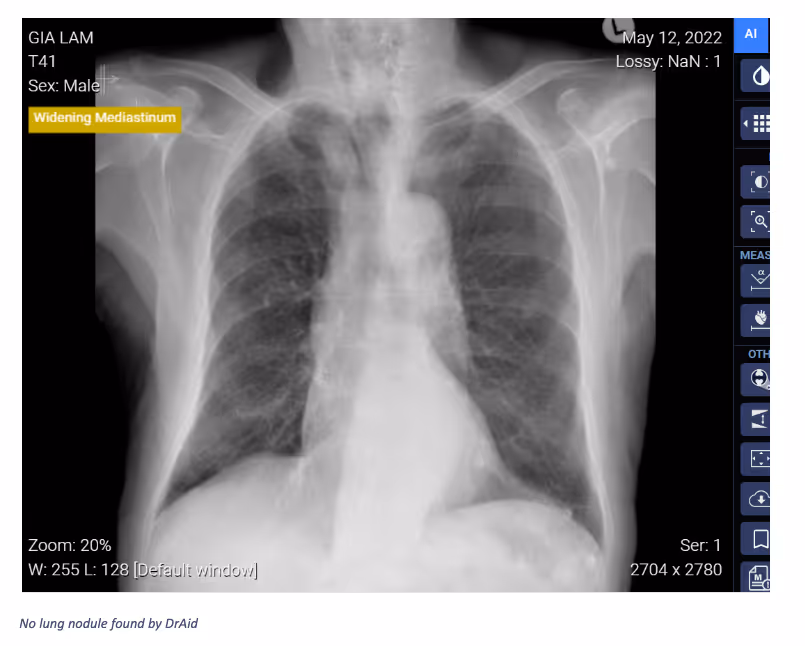

Ferrum Health partners with best-in-class AI providers offering solutions designed to reduce radiology workload and improve patient care.VinBrain Case Study: Distinguishing Lung Nodule from Other Easily Confused LesionsIntroductionConfusion in distinguishing between similar-looking findings on x-ray images is a problem that can be encountered by physicians (e.g., sclerotic rib lesions can mimic pulmonary nodules). The key is to look at prior radiographs. If the nodule remains projected over exactly the same rib site despite projectional differences then the physician can be confident that the lesions are within the rib rather than the lung.Clinical CaseAn 85-year-old male patient presented to the hospital with “Recent TAVI (transcatheter aortic valve implantation). A chest x-ray was required with both AP and PA views, then CT. After screening these images, a nodule was projected in the left mid-zone. The nodule “moves'' relative to the lung but remains directly associated with the anterior aspect of the left fourth rib on both the PA and AP projections. This indicated that the lesion is associated with the rib, which was confirmed by looking at the patient’s prior TAVI planning CT. Finally, based on CT images, the physician confirmed the Sclerotic lesion within the anterior aspect of the left 4th rib.

ConclusionDrAid can distinguish lung nodules from other easily confused lesions, which helps reduce false positives and reduce imaging scans needed for normal diagnosis purposes.Interested in deploying DrAid at your health facility?Contact the Ferrum Health team to learn more.